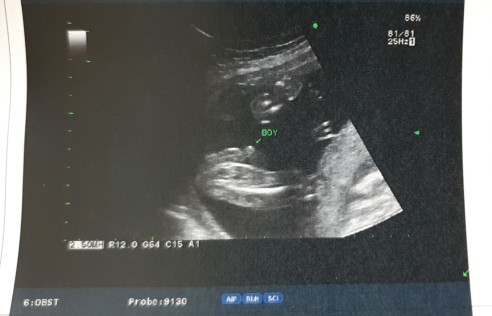

ในภาพเป็น ผช ใช่ไหมค่ะ พอดีหมอขอชัวร์ๆ เดือนหน้า เลยสอบถามแม่ๆ ที่มีประสบการณ์ลูกชาย หน่อยค่ะ ?ขอดูใบอัตตลาซาวเด็ก ผช . หน่อยจร้าาา? ถาพไม่ชัดเพราะถ่าย VDO มาจร้า ??

หมอบอกผู้ชายค่ะ

ตรงลูกศรเลยค่ะ

ชี้โด่มาเลยจ้า